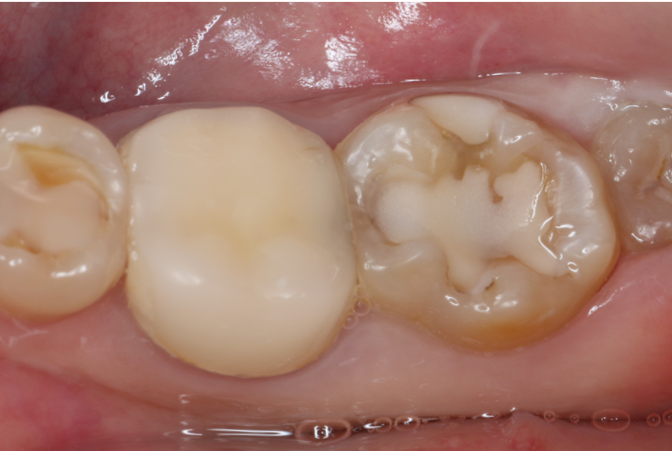

症例1

| 項目 | 詳細 |

|---|---|

| 患者様データ | 30代 女性 |

| 来院時の主訴 | 「右下の歯の治療後から違和感が続いている。」 |

| 医院の診断 | 虫歯の再発、慢性根尖性歯周炎、近心根パーフォレーション |

| 通院期間 | 6ヶ月 |

| 来院回数 | 8回(定期的なチェック含む) |

| 治療費 | 240,000円(税抜) 《内訳》 精密感染根管治療100,000円、ファイバーポストコア20,000円、セラミック治療120,000円 |

| リスクと副作用 | ①根管治療歯は長期的には破折するリスク ②メインテナンスが必要 |

| ココがこだわりのポイント☝ |

ラバーダム防湿とマイクロスコープを使用して丁寧に治療を行いました。 再根管治療のため、殺菌性があり歯を補強することのできる根管充填材料を使用しています。 |